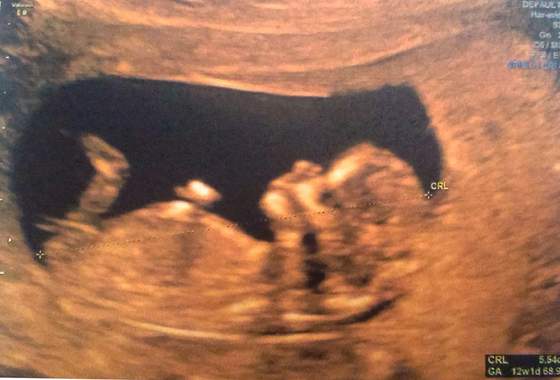

My też po prenatalnych i wsio ok. Mały ma 72 mm do dupeczki ale płci nie było widać. Czarna plama na brzuchu to żoładek i lekarz się śmiał, że ostro nażarty :))))

Załączniki

• 20140711_182705.jpg

20140711_182705.jpg

32,8 KB · Wyświetleń: 66